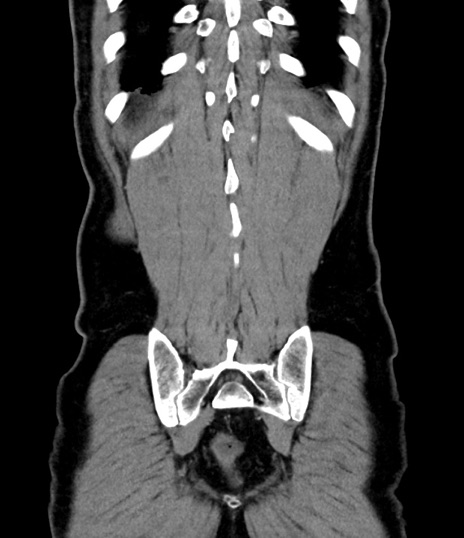

症例8(冠状断像)

【症例】 60歳代男性

【主訴】 黒色吐物

【現病歴】 4日前から嘔気自覚、2日前の朝食後にも嘔気あり、自分で手で嘔吐反射起こし嘔吐したところ血が混ざっていたため受診。

【既往歴】 5年前汎発性腹膜炎を伴う急性虫垂炎で手術、高血圧、前立腺肥大症、高脂血症

【身体所見】 腹部正中に手術癩痕あり 腹部平坦・軟圧痛なし膨満感あり

【データ】WBC 8400、CRP 4.54